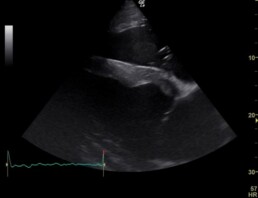

In der elektrokardiographischen und echokardiographischen Untersuchung zeigten sich die geringgradige Mitralklappeninsuffizienz (Schlussunfähigkeit der Herzklappe zwischen linkem Vorhof und linker Herzkammer), die geringgradige Trikuspidalkappeninsuffizienz (Herzklappe zwischen rechtem Vorhof und rechter Herzkammer), die geringgradige Aortenklappeninsuffizienz (Herzklappe zwischen linker Herzkammer und Aorta, Abb. 2) und das Vorhofflimmern (Herzarrhythmie) als unverändert. Die Herzdimensionsveränderungen liegen weiterhin vor, sind jedoch unverändert bis geringgradig verbessert (Abb. 1, 3).

Abb. 1: 4-Kammerblick, bei einer Eindringtiefe von 30 cm (sichtbare kugelige Herzform infolge der Dimensionsveränderungen)